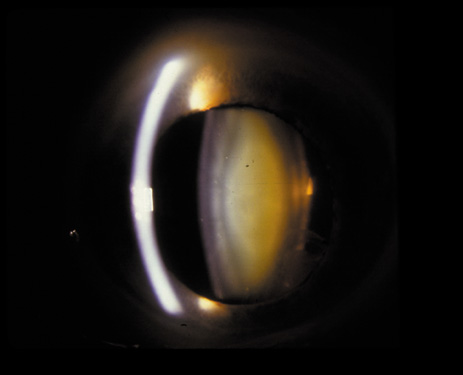

Nuclear cataracts tend to progress slowly. The refractive index of the lens changes as the nucleus progressively hardens, which usually results in increasing myopia.20,21 In some patients this is accompanied by optical distortion, especially of distant images, while near vision remains unaffected. A nuclear cataract is best seen with the narrow-beam direct illumination employed by the slit-lamp, which reveals the color and generalized haze or opalescence of the nucleus. In the early stages, the two halves (cotyledons) of the embryonic nucleus remain visible (Fig. 3). Later the entire nucleus appears as a homogeneous mass in contrast to the cortex (Fig. 4). Retroillumination may show the “oil droplet” effect (Fig. 5). Sometimes one may notice crystals in the lens nucleus (known as a Christmas tree cataract; Fig. 6A and B).

Fig. 5. “Oil droplet” appearance of a pure nuclear cataract seen on retroillumination examination.